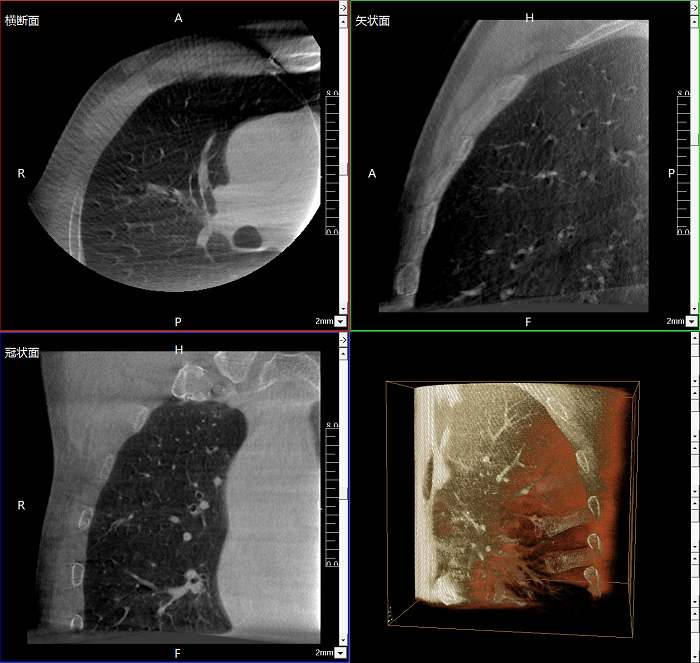

三維成像 全面觀(guān)察

任意視角、任意切面觀(guān)察

術(shù)中實(shí)時(shí)生成橫斷面、矢狀面、冠狀面及三維影像,可在任意切面、任意角度評估植入物和解剖結構的相對位置。

術(shù)中CT檢查 減少翻修概率

通過(guò)術(shù)中三維影像的檢查,可以立即發(fā)現植入物的錯位,減少不必要的第二次手術(shù),減少并發(fā)癥概率以及感染風(fēng)險。

Clinical picture

臨床圖片